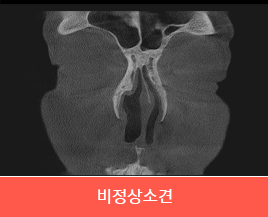

비중격만곡증에

의한 비염 |

비중격만곡증에 의한 비염일 경우

비중격 연골이 휘어서 생긴 비염은 휘어진 비중격

연골을 교정하면서 비염 수술을 같이 해야 합니다. |